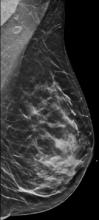

In addition to women with dense breasts, there are also other women for whom mammographic screening is not really enough, which is why research needs to continue in this field. Dr. Wendie Berg, a leading breast cancer specialist, talks with ITN about new research and advancements in breast imaging technology.

Dr. Berg, MD, PhD, FACR, FSBI, is Professor of Radiology at the University of Pittsburgh School of Medicine and Magee-Womens Hospital of UPMC, specializing in breast imaging. She is also the Chief Scientific Advisor to DenseBreast-info.org. A renowned expert, she writes and co-edits one of the leading textbooks on the topic, Diagnostic Imaging: Breast, currently in its third edition, and has co-authored over 120 peer-reviewed research publications.

Breast Density | April 14, 2023

It has long been said that a national reporting standard is needed in order to ensure all American women receive at least the same basic information regarding breast density, and a spotlight put on the importance of routine breast imaging. Dr. Wendie Berg, a leading breast cancer specialist, shares with ITN what is being done in the fight against breast cancer and the importance of this standardization in reporting for women.